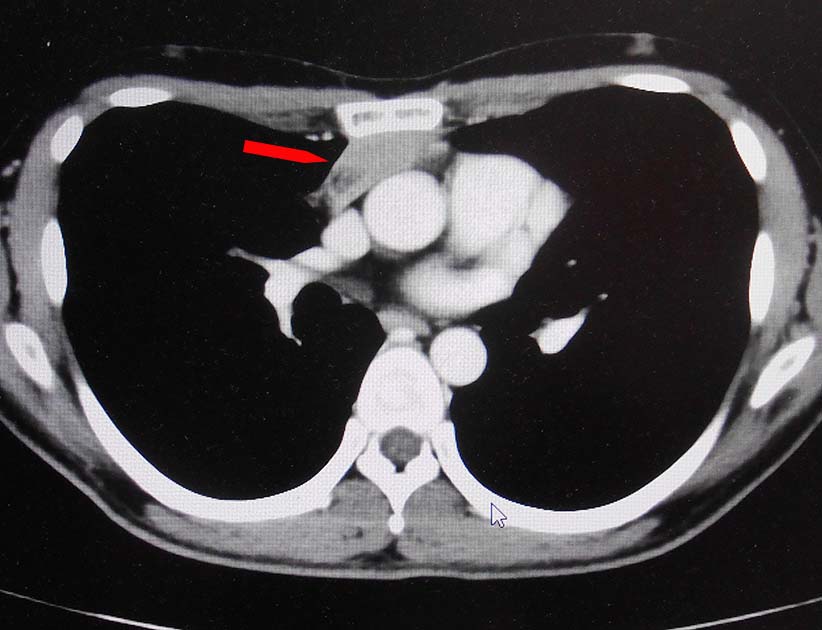

無痛性精巣腫大で泌尿器科受診. 画像診断では, 左精巣最大径4.5cmの腫瘤で縦隔リンパ節転移が疑われた. 左高位精巣摘除術をうける.

前縦隔や右心横隔膜角部に不定形, 不均一でべたっとした腫瘤状軟部濃度域を認める. 節外浸潤を伴ったリンパ節転移の可能性を考える.

画像: 左精巣腫瘤. 縦隔リンパ節転移疑い.